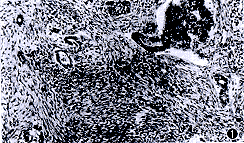

發病機制明確的遺傳性乳腺癌-卵巢癌綜合徵者,在病理分類上以漿液性囊腺癌為主。BRCA1在腫瘤發生中的作用及調節機制還不十分清楚,認為BRCA1是一個腫瘤抑制基因編碼抑癌蛋白,對腫瘤生長產生降調節起到抑制腫瘤生長的作用。但是大多數早發性家族性乳腺癌與卵巢癌都有BRCA1生殖細胞基因突變。BRCA1攜帶者在50歲時發生乳腺癌和卵巢癌的風險分別為73%和29%。有BRCA1基因存在者,當其發生癌基因突變,BRCA1表達下降則具有較高的患乳腺癌和卵巢癌的風險度,也易發生該類有關的癌腫。

遺傳性乳腺癌-卵巢癌綜合徵重要特徵是發病年齡早,根據其定義,該綜合徵表現為:在有乳腺癌傾向的家族中乳腺癌患者或其1、2級血親中有兩個或兩個以上的卵巢癌患者並有以下臨床特點:①家族中乳腺癌多呈早發表現,一般發病年齡<50歲;②家族中卵巢癌患者發病年齡也較早,一般為49.6~55.3歲,平均52.4歲(散發性卵巢癌的發病年齡平均為59歲);③家族中可有其他類型腫瘤患者,如子宮內膜癌消化道癌、前列腺癌等;④卵巢癌的病理類型以漿液性乳頭狀囊腺癌為多見

組織病理學檢查突變基因BRCA1和BRCA2測定為陽性結果